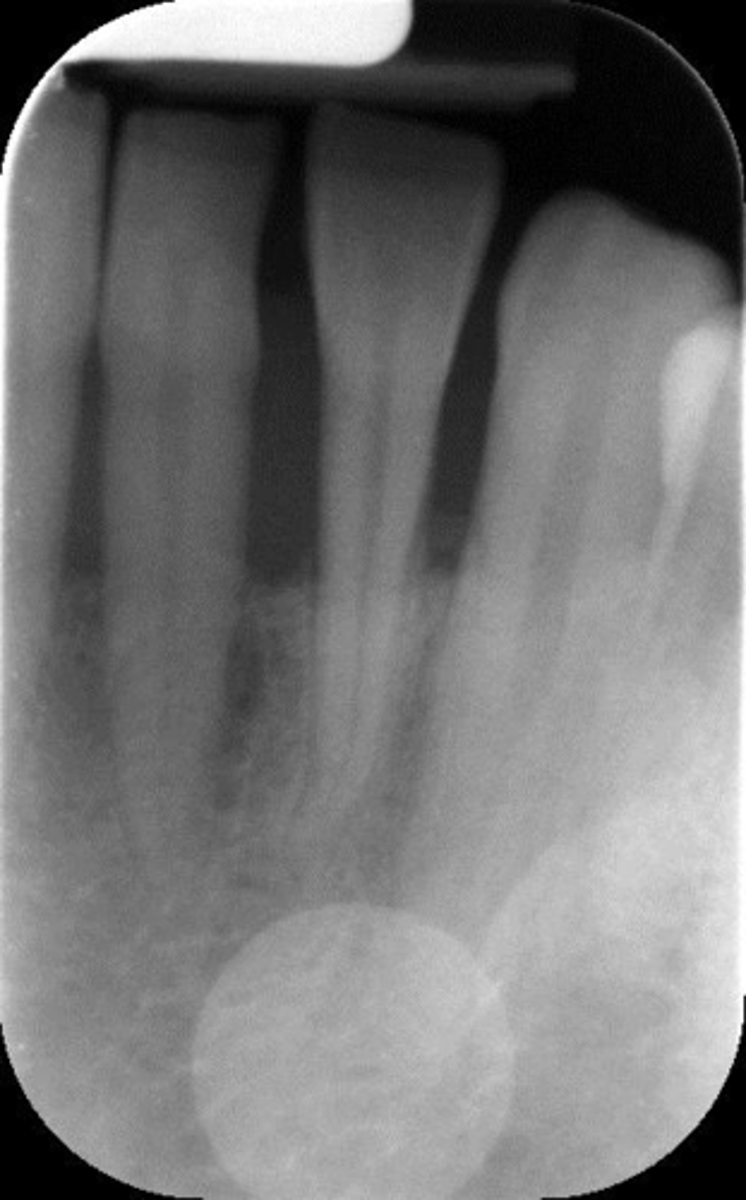

Rinn instrument bar, vertical angulation

What is this error?